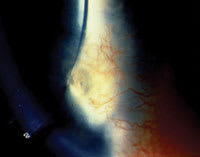

| Figure 1. Patient's VLK lesion OD. |

Figure 1 shows the VLK lesion OD prior to biopsy. Following the biopsy, the specimen was placed in formalin and stained with PAS for further study.